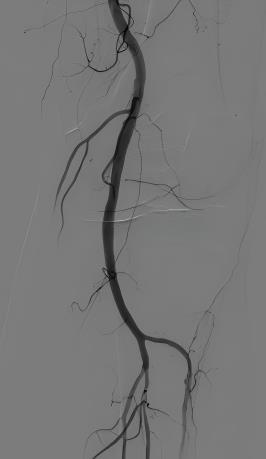

来国药东风总医院就诊时,血管造影显示了一个严峻的现实——郝伯伯左侧腘动脉狭窄达90%,双侧胫前动脉闭塞。这正是导致他剧痛和行走困难的根源。

下肢动脉介入治疗前

介入治疗后